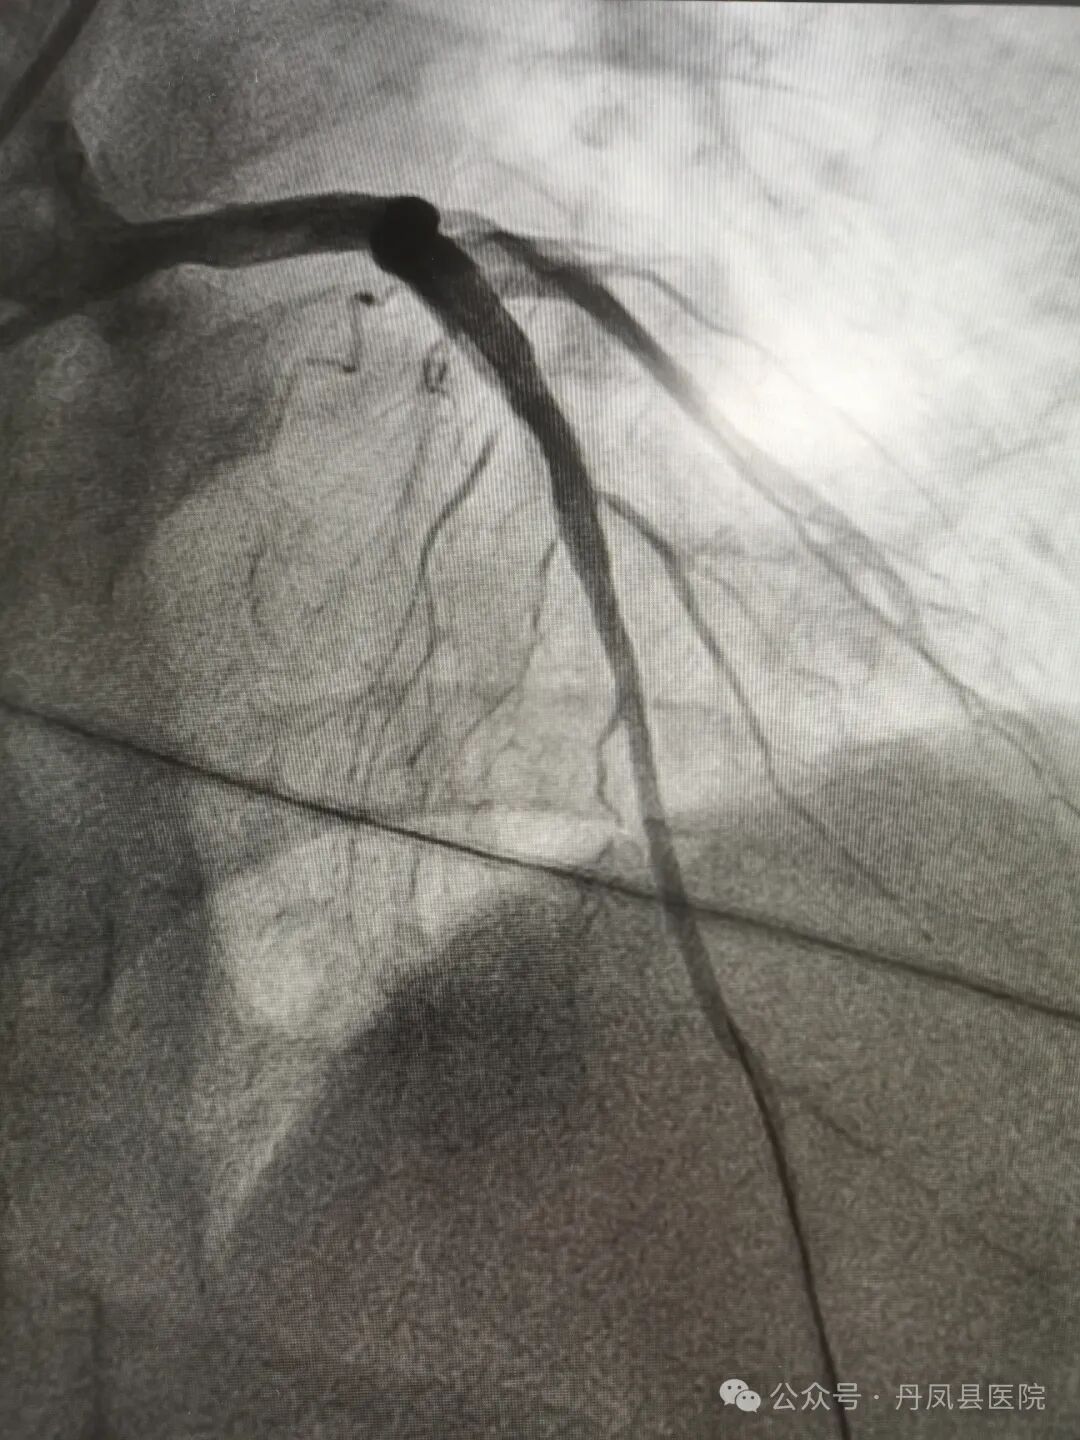

图1、图2为造影下发现病变,图3为术中球囊释放,图4为球囊释放后。